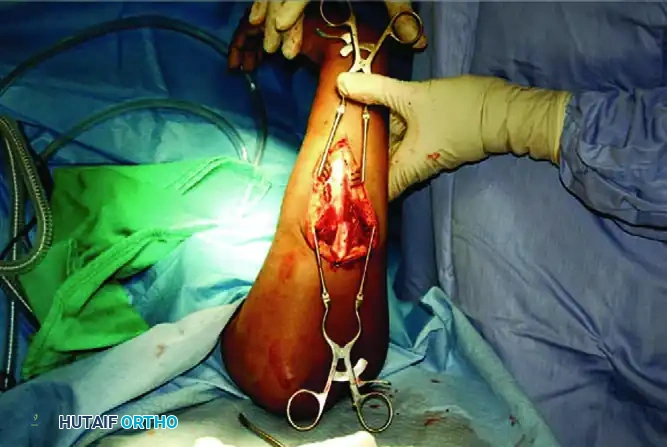

SURGICAL TECHNIQUE: STEP-BY-STEP ORIF

1. Exposure and Debridement

Following the chosen surgical approaches, expose the fracture sites. It is imperative to preserve the periosteum along the proximal and distal segments to maintain the osteogenic potential of the bone. Do not strip the periosteum beyond what is absolutely necessary for plate application. Débride the fracture edges, meticulously removing interposed hematoma, muscle, and devitalized debris to allow for intimate cortical contact.

3. Fracture Reduction and Plate Application

4. Ulnar Fixation and Final Assessment

After the radius is secured, proceed to the ulna using the same plating strategies (compression, neutralization, or bridge plating). Once both bones are rigidly stabilized, assess forearm pronation and supination clinically. The motion should be smooth and unimpeded.

Confirm adequate reduction, restoration of the radial bow, and proper hardware placement with orthogonal fluoroscopy. Ensure no screws are penetrating the radioulnar joints.

5. Closure

Irrigate the wounds copiously. Close the deep fascia only if it does not create compartment tension; otherwise, leave it open. Close the subcutaneous tissues and skin in a standard fashion.